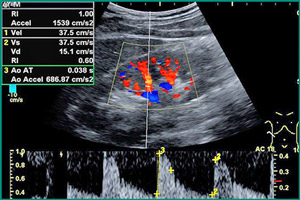

Ультразвуковая диагностика является основным методом обследования почек. С помощью ультразвука можно определить форму, размеры, структуру и толщину стенок почек, а также их расположение и взаимодействие с соседними органами. Ультразвуковая эхография также позволяет оценить состояние паренхимы почек и чашечно-лоханочного аппарата, обнаружить наличие камней, опухолей и смещение органов. Допплерография, или ультразвуковое исследование сосудов, помогает оценить состояние вен и артерий почек и выявить повреждения. Существуют различные виды допплер-сканирования, включая цветное, тканевое и энергетическое, которые применяются для разных целей. Ультразвуковая диагностика почек доступна для всех и может быть проведена по рекомендации врача или по собственному желанию.